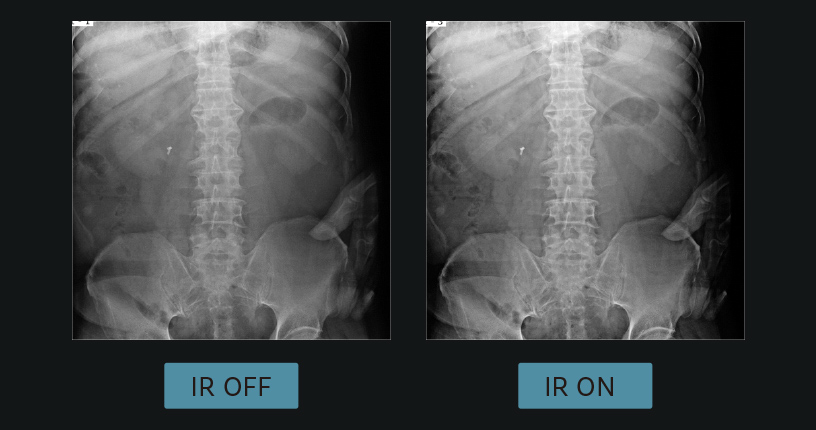

RealtimeIRは逐次近似を用いたノイズ低減処理です。RealtimeIRとHARMONYを併用することで24%もノイズを低減します。Retinex理論(局所コントラスト補正)を効果的に適応でき、低ノイズで高コントラストな画像を提供します。